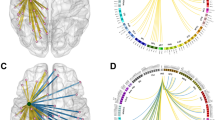

Compared with HC, patients with unilateral hippocampal glioma exhibited significantly larger gray matter volume in the contralesional hippocampus and parahippocampal regions (cluster = 571 voxels for HipL; cluster 1 = 538 voxels and cluster 2 = 88 voxels for HipR; family-wise error corrected p < 0.05). No significant alterations were found in control regions. Volumetric analyses showed the same trend in the contralesional hippocampal subregions for both patient groups, including the CA1 head, CA3 head, hippocampus amygdala transition area (HATA), fimbria, and the granule cell molecular layer of the dentate gyrus head (GC-ML-DG head). Notably, the differences of the contralesional HATA (HipL: η2 = 0.418, corrected p = 0.002; HipR: η2 = 0.313, corrected p = 0.052) and fimbria (HipL: η2 = 0.450, corrected p < 0.001; HipR: η2 = 0.358, corrected p = 0.012) still held after the Bonferroni correction.

Our findings provide evidence for macrostructural plasticity of the contralateral hippocampus in patients with unilateral hippocampal glioma. Specifically, HATA and fimbria exhibit great potential in this process.

• Glioma infiltration of the hippocampal regions induces a significant increase in gray matter volume on the contralateral side.

• Specifically, the HATA and fimbria regions exhibit favorable plastic potential in the process of lesion-induced structural remolding.